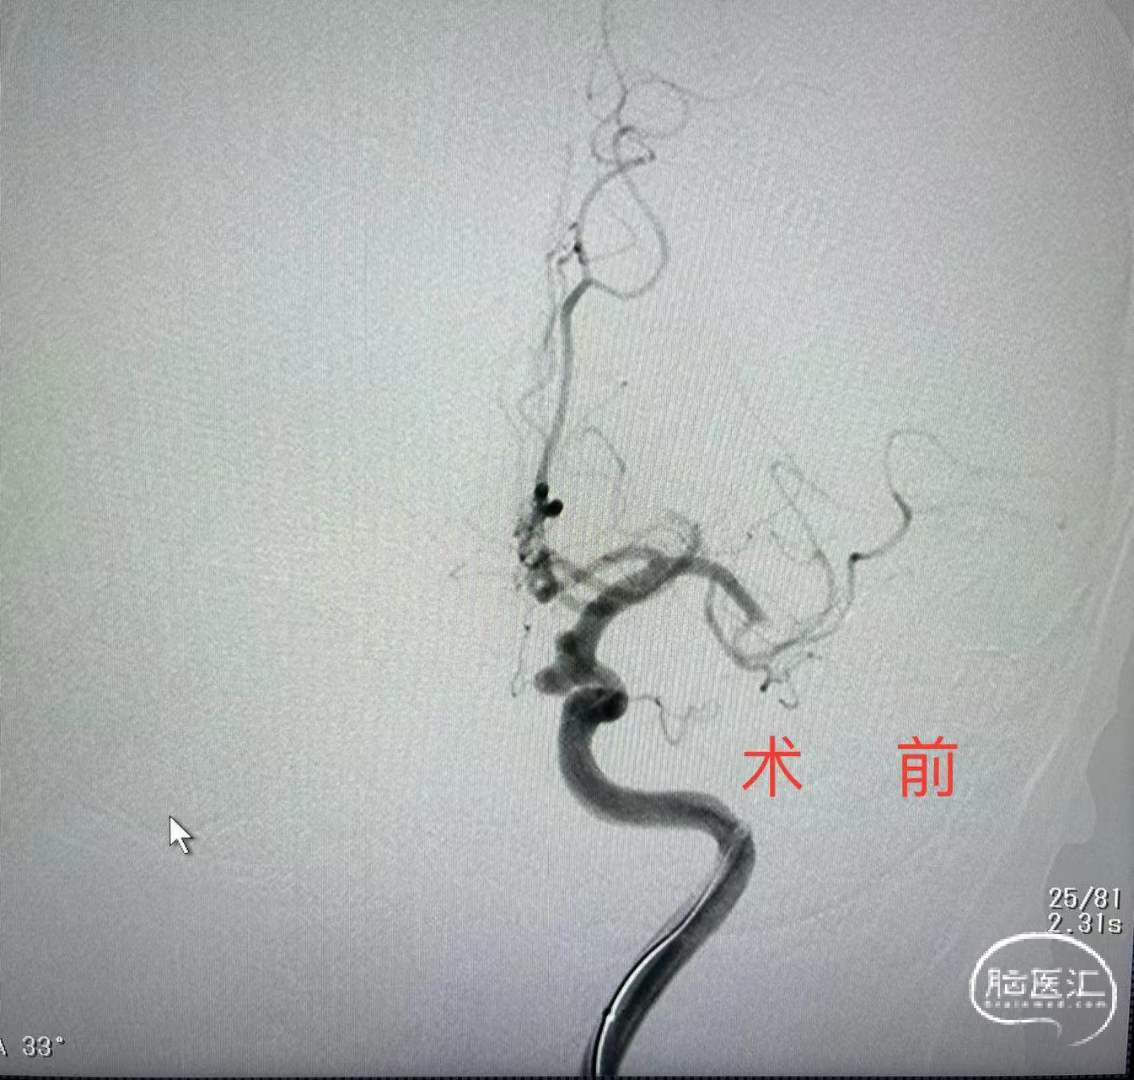

此例为宽颈动脉瘤,家属要求行血流导向装置植入术。术中刚刚置好通路,突发大脑中动脉梗塞,紧急予以抽栓术,术后通畅,最后再植入密网支架。